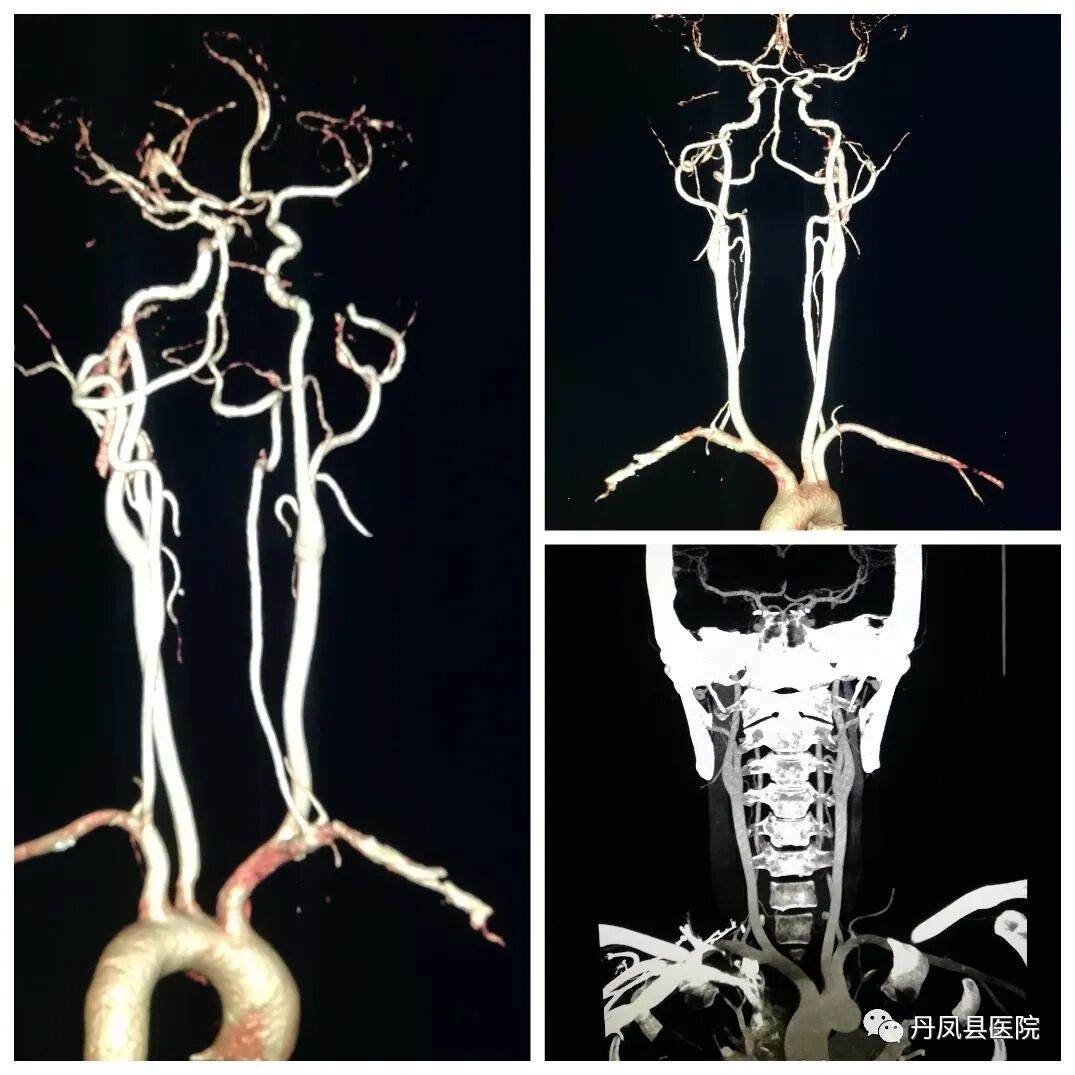

头颈部血管CTA

头颈部血管CTA是近年来发展较快的非创伤性血管造影技术,其在诊断颈部、脑血管病变、畸形等方面均显示了无可比拟的优越性,CTA在显示大脑前、中、后及前交通动脉方面敏感性可达89%~100%,该检查无动脉损伤及卒中风险,可很好显示血管壁钙化,能旋转360度,多方位、多角度对血管进行观察,避免血管重叠的干扰,可清晰显示颈内动脉、椎动脉起始段的钙化、扭曲和狭窄。普通放射